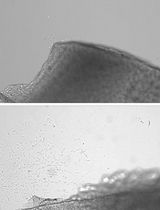

7. Decapitate the fetus, place it in the left lateral recumbent position (Figure 1a), and make a longitudinal incision in the right thoracoabdominal wall to expose the thoracic and abdominal cavities. Avoid damaging the visceral organs.

8. Extend the incision toward the umbilicus. Trace the umbilical vessels—running alongside the bladder toward the common iliac arteries to locate the bladder (Figure 1b).

12. Peel the back, including the vertebral column, away from the trunk, ensuring the abdominal aorta remains with the trunk to prevent detaching the kidneys. If the kidneys separate with the back, the bladder remains in the trunk, and the ureters will be severed (Figure 1c).

13. After peeling away the back, excise the bilateral mesonephroi and adrenal glands (Figure 1d).